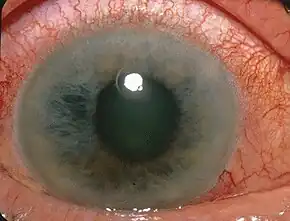

Glaucoma: Glaucoma is a collection of diseases that damages the nerve in the eye / retina. The damage in the nerve has the possibility to cause blindness. You may not know you have a Glaucoma without an in-depth eye exam normally using the dilation method. There is no cure for a Glaucoma, but it may be treated if found early. It is unknown the cause of a Glaucoma, but those who may be at risk include:

- Individuals over the age of 60 (most commonly those who are Hispanic or Latino)

- African Americans over the age of 40 years old Individuals with a family history of Glaucoma's.[9]